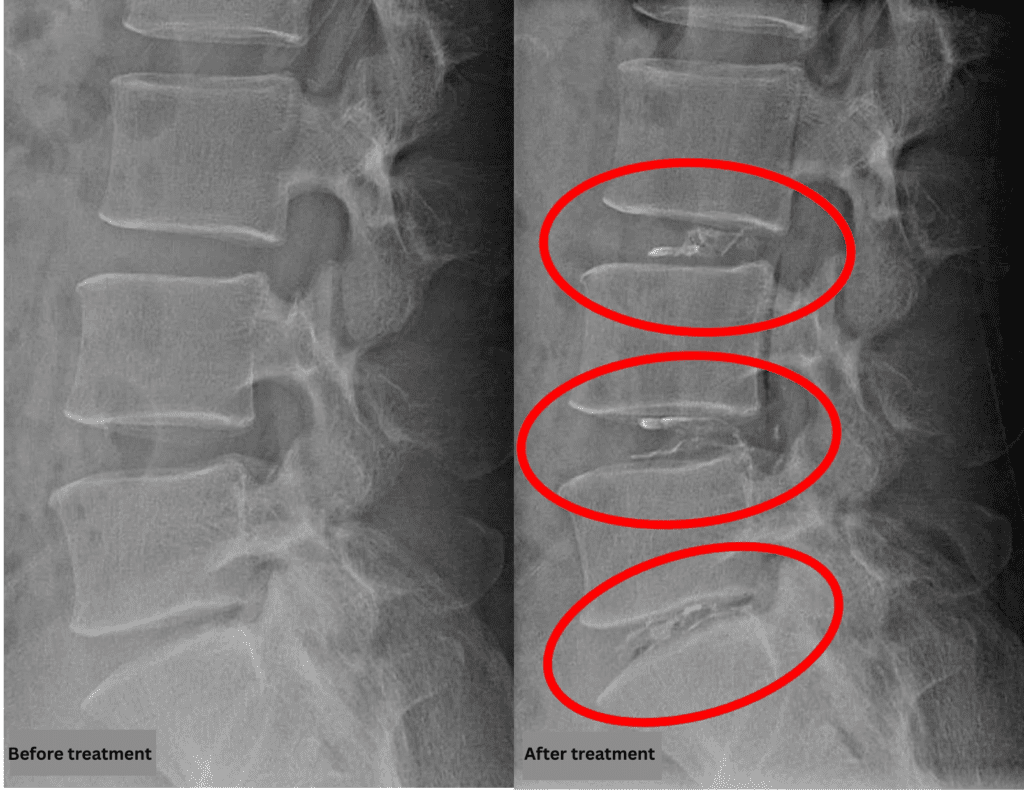

- L3/4, L4/5: Disc degeneration

- L5/S: Disc degeneration, disc bulging, foraminal stenosis, endplate degeneration

The above findings were also observed on the imaging.

Compression of the spinal canal due to disc pathology at L3/4, L4/5, and L5/S was considered highly likely to be the cause of the patient’s symptoms.

After consulting with the patient, the Cellgel Method was performed on L3/4, 4/5 and 5/s.